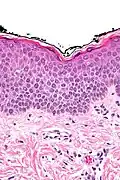

In der histologischen (lichtmikroskopischen) Untersuchung einer Gewebeprobe aus erkrankter Haut weist das Ekzem die Merkmale einer spongiotischen Dermatitis auf. Analog zum klinischen Bild zeigt sich ein charakteristischer Verlauf der Veränderungen:

Akute Phase: In der Oberhaut (Epidermis) zeigt sich eine Gefügelockerung durch ein interzelluläres Ödem (Spongiose), das bei starker Ausprägung zur Ausbildung von kleinen, aber auch größeren Blasen (Vesikel bzw. Bullae) führen kann.

Als Kratzeffekt besteht eine überschießende und eventuell auch gestörte Verhornung (Hyperkeratose bzw. Parakeratose) mit überliegender Schuppenkruste (parakeratotische Hornschicht mit eingeschlossenen Serumresten). Auch die oberen Anteile der Lederhaut (Dermis) sind durch ein Ödem gelockert, hier finden sich außerdem weitgestellte kleine Blutgefäße (Kapillaren). Um diese Gefäße bilden sich Ansammlungen aus Entzündungszellen, die sich hauptsächlich aus Lymphozyten und Histiozyten, nicht selten auch eosinophilen Granulozyten (Untergruppen der weißen Blutkörperchen) zusammensetzen. Lymphozyten wandern teilweise auch in die Epidermis ein (lymphozytäre Exozytose).

Als Reaktion auf den anhaltenden Entzündungsreiz und juckreizbedingtes Kratzen kommt es in der Folge zur Verbreiterung der Epidermis (Akanthose) mit Rückgang der Spongiose. Anfangs eventuell vorhandene größere Blasen gehen zurück, und es verbleiben nurmehr kleine Bläschen. Zumeist besteht jetzt eine ausgedehnte Parakeratose, und im Randbereich oberflächlicher epidermaler Defekte (Erosionen) können auch neutrophile Granulozyten (Untergruppe der weißen Blutkörperchen) in der Epidermis zu sehen sein. Dieses Zwischenstadium wird gelegentlich auch als subakute Phase bezeichnet.

Chronische Phase: es überwiegen die Zeichen der chronischen mechanischen Irritation mit Lichenifikation: epidermal zeigt sich eine deutliche Akanthose mit Verbreiterung der Granularzellschicht (Hypergranulose) und Hyperkeratose. Die Spongiose geht weiter zurück und kann in diesem Stadium nur noch sehr schwach ausgeprägt sein. Das der Epidermis unmittelbar unterliegende Bindegewebe der oberen Dermis (Stratum papillare) zeigt eine Vermehrung von Kollagenfasern (Fibrose), die senkrecht zur Epidermis ausgerichtet sind.[5]

Spongiose: Gefügelockerung der Epidermis mit sichtbaren Spalten zwischen den einzelnen Zellen durch interzelluläres Ödem -

Vesikelbildung: bei starker Spongiose lösen sich die Zellen voneinander und es bilden sich kleine Bläschen

Hyperkeratose: der Epidermis aufgelagert besteht eine verbreiterte Hornschicht. In der Dermis Kapillaren mit umliegenden Entzündungszellen

Parakeratose: die Hornschicht enthält Reste von Zellkernen als Zeichen der gestörten Verhornung